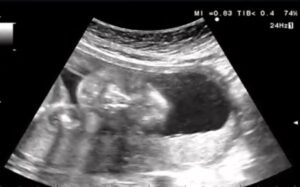

妊娠22週4日のエコー検査の際、画面に映し出された赤ちゃんはあくびをしていました。

エコー中は毎回元気に動き回っていることが多かったのですが、最後に大あくびを見せた赤ちゃんに、先生もママさんも「元気すぎるくらいだね」と笑ってしまったそうです。